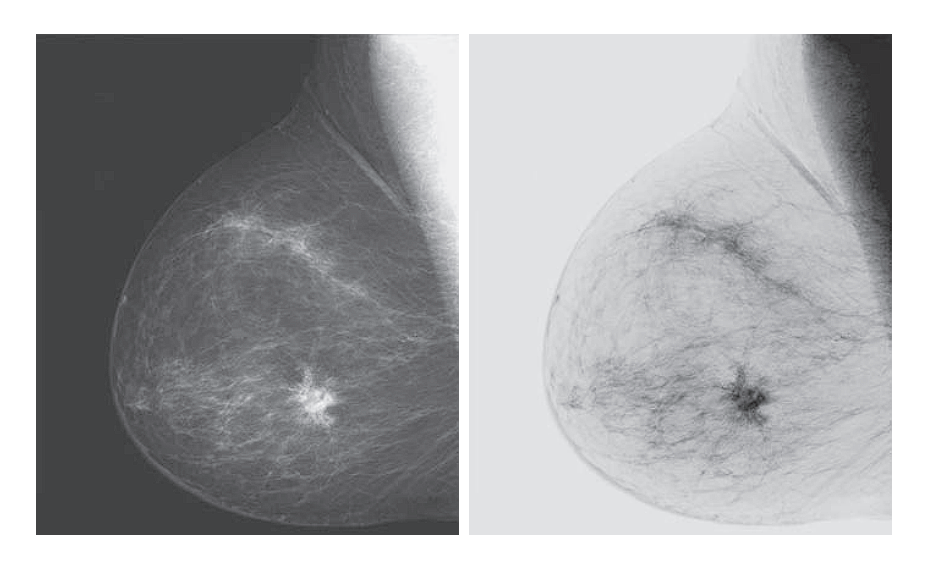

Image Negatives (Negative Transformation)

Definition:

The negative transformation inverts the intensity values of an image by mapping each pixel’s brightness to its opposite within the intensity range.

The transformation function is:

T(r) = L − 1 − r

Where:

ris the original intensity value (input pixel),T(r)is the transformed intensity (output),Lis the total number of intensity levels (e.g., 256 for 8-bit images).

Effect:

- Black becomes white, and white becomes black.

- Mid-gray values remain relatively unchanged.

- The dynamic range is reversed: the brightest parts become the darkest, and vice versa.

Applications:

-

Enhancing dark details in images with poor lighting.

Commonly used in:

- Medical imaging, such as X-rays or mammograms,

- Astronomical images to highlight faint stars or nebulae.

Example:

Original intensity value: r = 50

If L = 256, then:

T(50) = 255 − 50 = 205

The pixel becomes much brighter in the negative image.